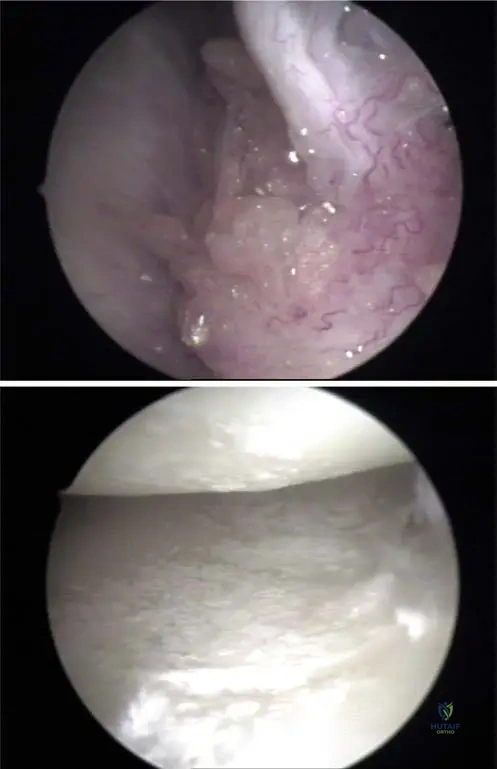

A 62-year-old male undergoes arthroscopy for chronic knee pain and suspected inflammatory arthritis. During the procedure, white, chalky deposits are noted within the joint.

View Answer & Explanation

Correct Answer: C

Rationale: The clinical context for Fig. 7.5 a, b states, "Deposits of urate crystals may occur in the synovium (a) and in the cartilage of the knee joint (b) as visualized by arthroscopy." This indicates that both these tissues are common sites for urate crystal deposition within the joint. While menisci are cartilaginous structures, the description is more encompassing of the joint's cartilage and synovium.

A 50-year-old male undergoes arthroscopy for chronic knee pain and suspected gout. During the procedure, the surgeon observes white, chalky deposits within the joint. According to the provided information, where might these urate crystals be found within the knee joint during arthroscopy?

Rationale: The clinical context for Fig. 7.5 a states, "Deposits of urate crystals may occur in the synovium (a) and in the cartilage of the knee joint (b) as visualized by arthroscopy." Therefore, finding crystals within the synovium is a correct arthroscopic observation. While they can also be in cartilage, "only" options are often incorrect, and synovium is a distinct location mentioned.

Question 43

During an arthroscopic examination of a 60-year-old male's knee, the surgeon notes glistening white deposits on the joint surfaces. These deposits are consistent with urate crystals. Based on the provided images and context, where else within the knee joint might these urate crystals be visualized arthroscopically?

Correct Answer: B

Rationale: The clinical context for Fig. 7.5 b states, "Deposits of urate crystals may occur in the synovium (a) and in the cartilage of the knee joint (b) as visualized by arthroscopy." Therefore, finding crystals on the articular cartilage is a correct arthroscopic observation. The other options are not mentioned as specific arthroscopic locations for urate crystal deposits in the provided text.